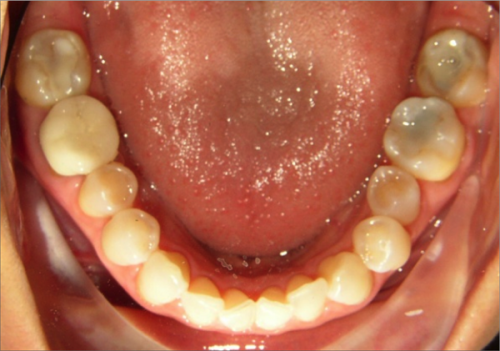

45 year old female:

Diagnosis:

- Missing upper left second bicuspid

- Lower arch crowding

- Edge to edge bite

Treatment:

- Extraction of upper & lower right second bicuspids

- Full fixed appliances

- 21 months